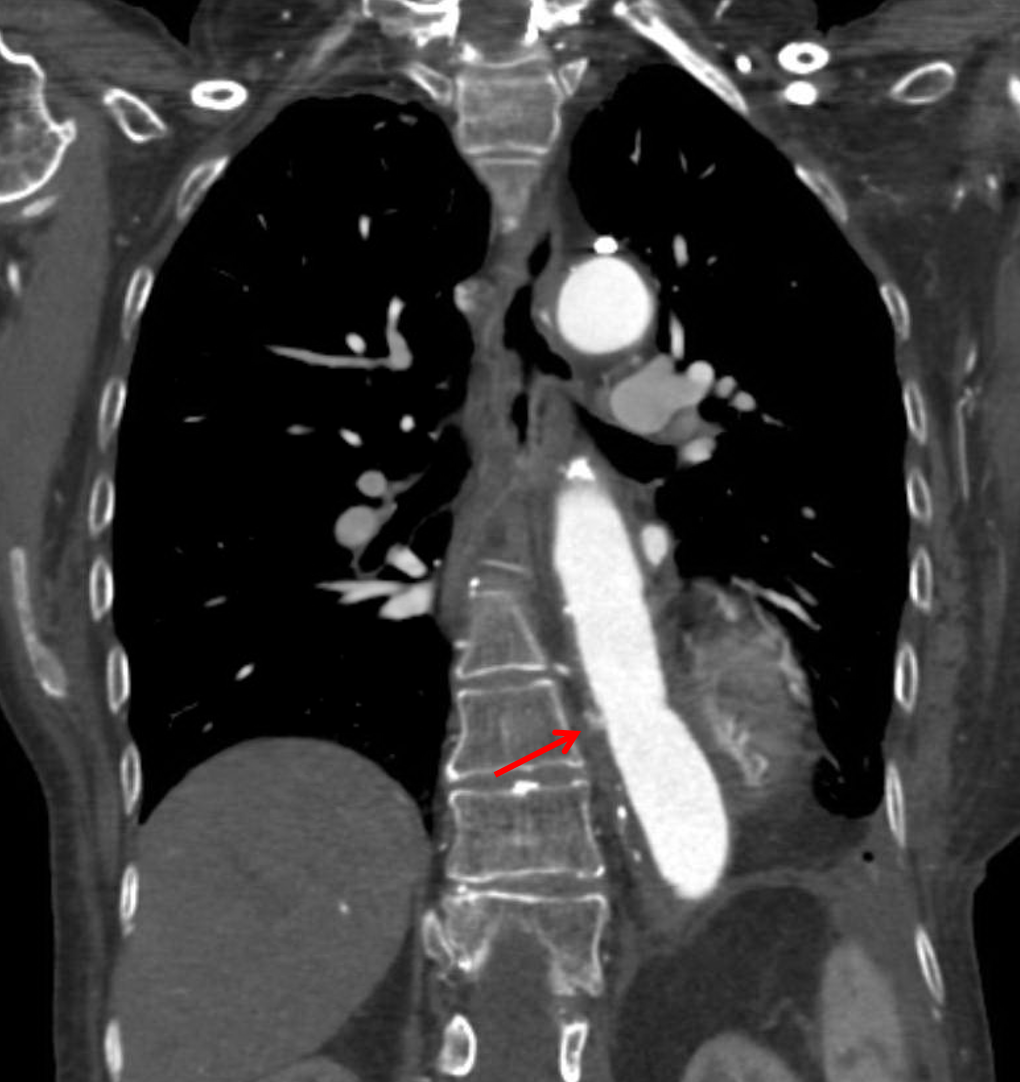

• Partially imaged surgical changes of graft repair of a thoracoabdominal aortic aneurysm with a small amount of intramural contrast leakage medially at the proximal anastomosis in the distal descending thoracic aorta

Partially imaged changes of graft repair of a thoracoabdominal aortic aneurysm with findings concerning for type 1A endoleak.

Focal contrast leakage along the medial aspect of the aorta along the proximal margin of the graft concerning for type 1A endoleak.